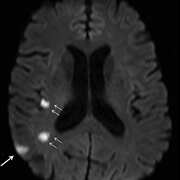

Πρόκειται γιά ασθενή ηλικίας 63 ετών με ιστορικό προσφάτου ισχαιμικού εγκεφαλικού. Στην αξονική τομογραφία διακρίνονται υπόπυκνες περιοχές στα αριστερά βασικά γάγγλια (περιοχή της ωχράς σφαίρας), στην κεντρική λευκή ουσία του αριστερού εγκεφαλικού ημισφαιρίου (ημι-ωοειδές κέντρο) και σε φλοιο-υποφλοιώδη περιοχή του αριστερού μετωπιαίου λοβού.